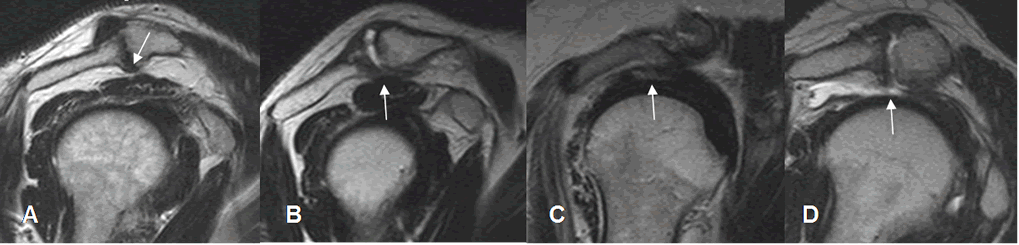

Fig 88. Cambios degenerativos en articulación acromioclavicular.

A, B, C y D: RM sagital en T2. Cambios degenerativos en la articulación acromioclavicular, en diferentes grados. En A sin contactar con el tendón del supraespinoso. En B, en contacto con el tendón, pero sin producir cambios. En C pinzamiento, con zona hiperintensa del tendón, por tendinitis o ruptura parcial y en D ausencia del tendón, por ruptura completa.